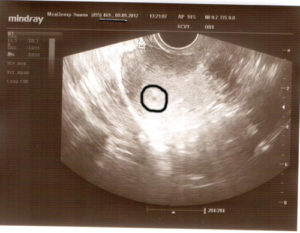

В ходе УЗИ плодное яйцо обнаруживается в виде маленькой черной точки. В нем хорошо видно расплывчатое белое пятнышко – эмбрион. Исследование проводят трансвагинальным способом.

Плодное яйцо представляет собой анэхогенное (не отражающее ультразвуковые волны) образование округлой или овальной формы. Микроскопические размеры эмбриона в самом начале его развития не дают возможности увидеть его с помощью УЗИ.

На ранних сроках сонолог выявляет беременность и определяет ее срок, обнаруживая плодное яйцо и измеряя его.

Когда яйцо хорошо визуализируется? На первых неделях плодное яйцо вырастает примерно на 1 мм в сутки: в 4 недели его диаметр составляет 3 мм, в 5 недель – 6 мм. До 8–10 недели беременности ее срок определяется по диаметру плодного яйца, затем – по копчико-теменному размеру (КТР) плода.